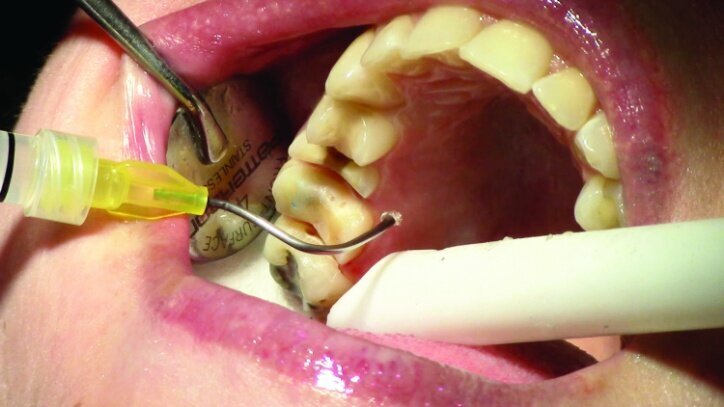

Tissue management was obtained with ViscoStat Clear, gingival haemostatic gel, 25 percent (m/m) aluminum chloride (Figs. 16 & 17). Gingival retraction was obtained using a two-cord system. First, a #00 size cord from Ultradent was placed on the mesial and distal of both preparations (Figs. 18 & 19).

Additional haemostatic gel was used prior to the second cord. The second cord was #2 size cord from Ultradent (Figs. 20 & 21a). A minimum of four minutes with both cords in place is needed for adequate retraction of the soft tissue (Fig. 21b).